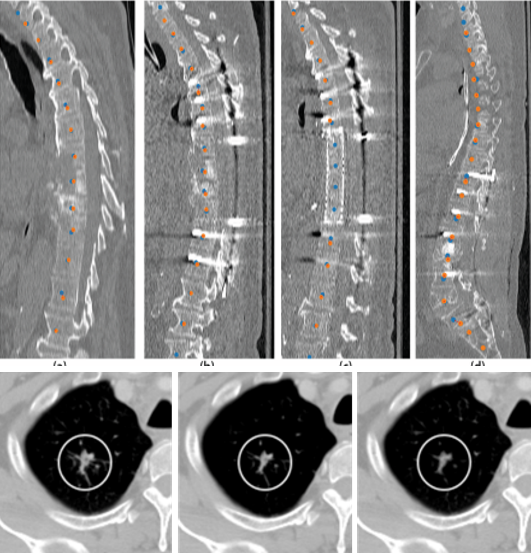

Medical imaging is now used extensively for accurate diagnosis, real-time intervention, and precision medicine. Our work has been focused on fast, high-resolution imaging augmented with functional and metabolic mapping. For example, dynamic 4D MRI under free breathing has been developed using PNCRNNs, with the reconstruction time as fast as 50 bin per second, offering substantial improvement of the image quality for dynamic golden-angle radial imaging of the abdomen. Novel imaging techniques have been developed for high-resolution whole-brain neurometabolic mapping, shedding light on in vivo molecular biomarkers for various brain diseases including stroke, brain tumor, and neurodegenerative disorders. A model-based deep learning architecture, referred to as MoDL-QSM, was developed with improved accuracy for quantifying tissue susceptibility for precise electrode implantation for deep-brain stimulation. To meet the demands for automated identification and localization of the vertebrae, pancreas, colon, lung nodules and other organs in low-dose CT, algorithms integrating local image details and global image patterns have been proposed. To extend the clinical use of nonlinear regression in medical imaging and image analysis, a deep negative correlation learning framework has been proposed to yield a deep regression of ensemble where each base model is both accurate and generalisable.

Vertebrae identification and localization

Chen Y, Gao Y, Li K, Zhao L, and Zhao J. Vertebrae identification and

localization utilizing fully convolutional networks and a hidden Markov model.

IEEE Transactions on Medical Imaging, 2020, 39(2): 387-399.